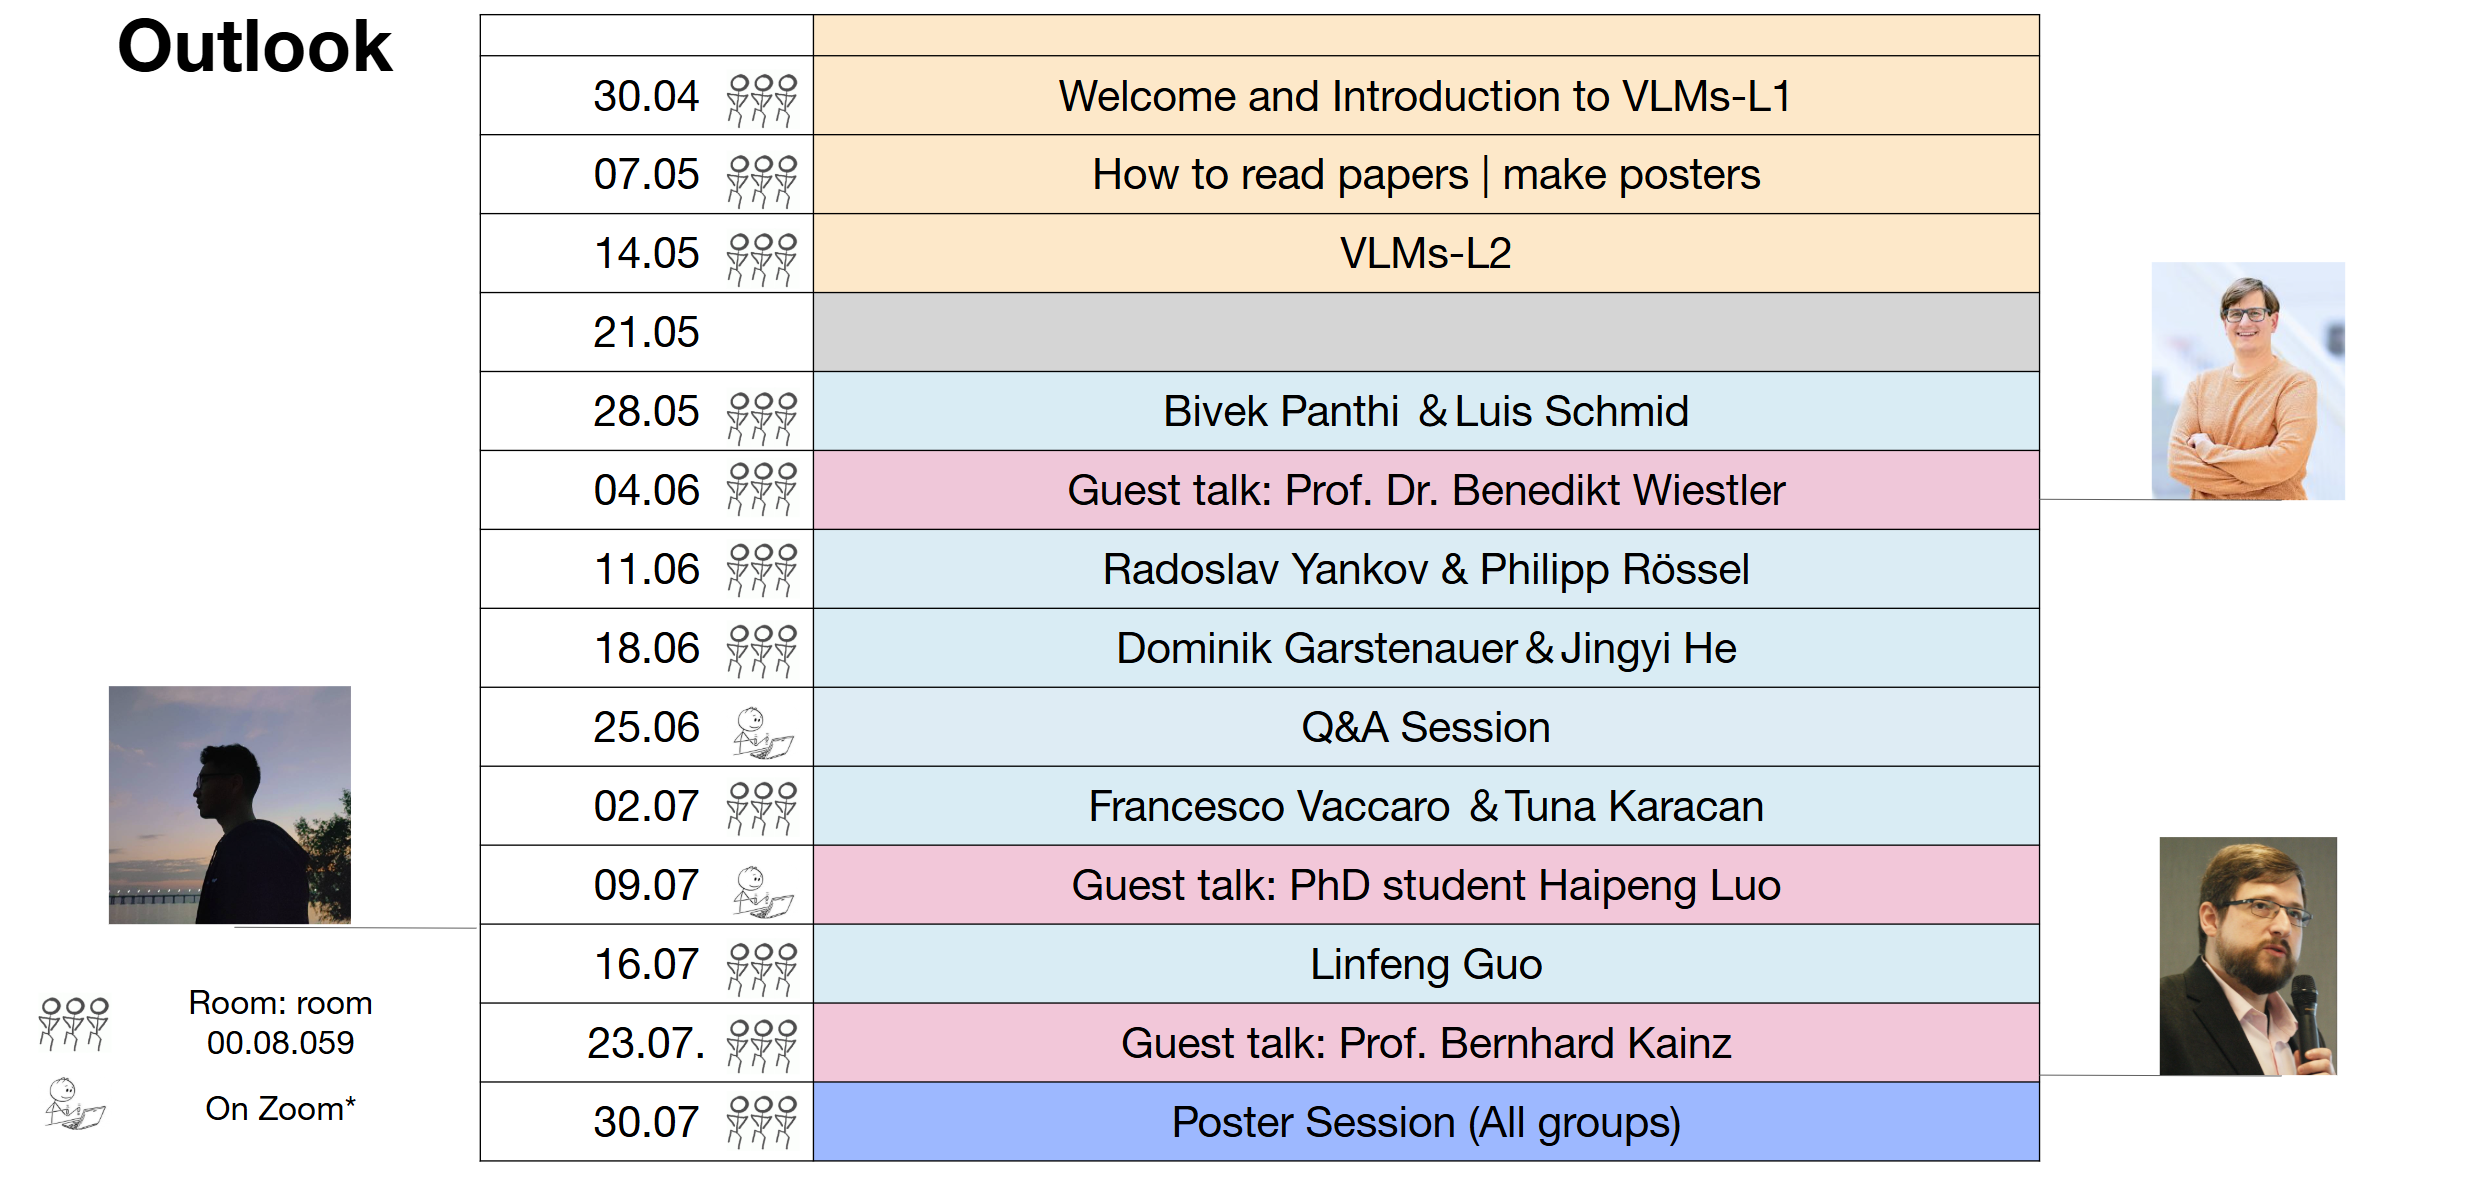

[04.2025] My new seminar 📚 AI for Vision-Language Models in Medical Imaging (IN2107, IN45069) is now open! For more details, please visit the course GitHub repository.

- (S 25) Master seminar, Technical University of Munich.

- Course ID: IN2107, IN45069.

- (S 24/25) Master seminar, Technical University of Munich.

- Course ID: IN2107.